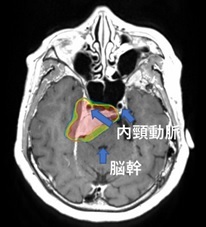

髄膜腫。内頸動脈を巻き込み脳幹を圧迫している。

放射線治療で増大を抑止し症状が出現するのを予防する。